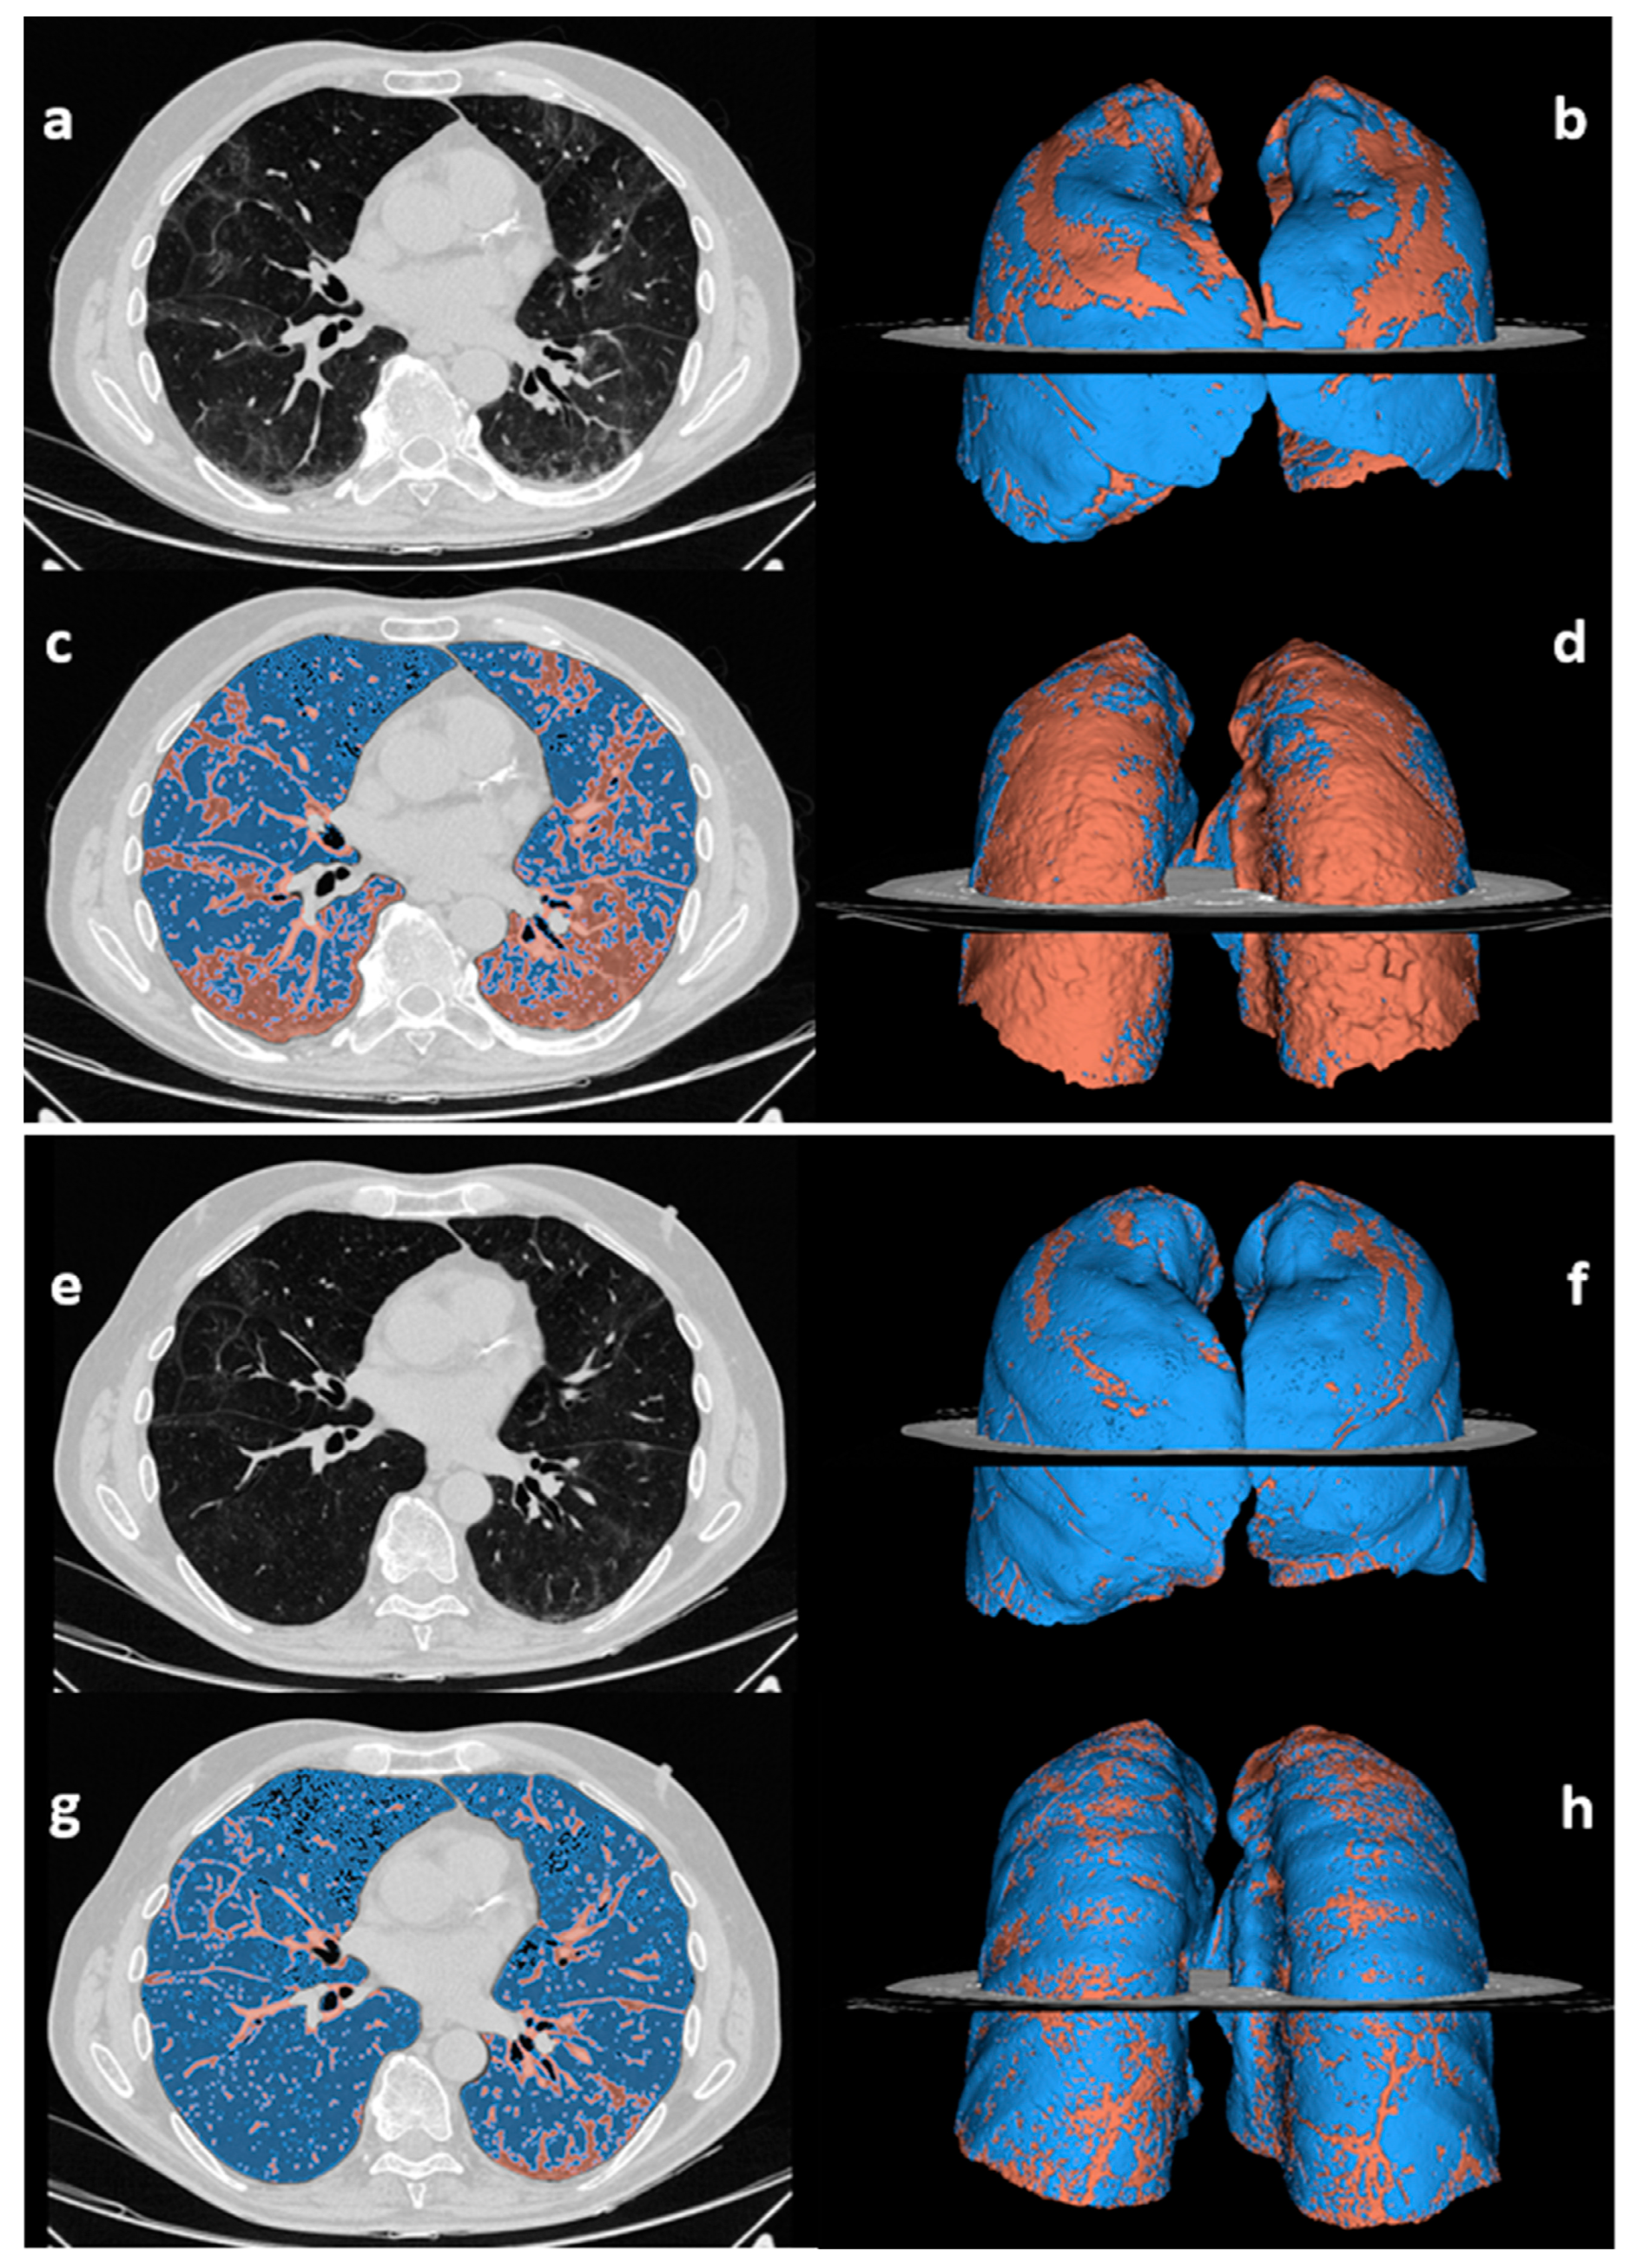

| No. of abnormal chest CT scans | 49/63 (78%) | 48/63 (76%) * | 1.000 |

| % of compromised lung volume | 14.4 [10.6–21.2] | 12.3 [9.2–15.9] | <0.001 |

| Type of CT pattern | 0.038 | ||

| GGO | 8 (16) | 2 (4) | |

| Reticular | 31 (63) | 38 (79) | |

| Combined | 10 (21) | 8 (17) | |

| Consolidation | 2 (4) | 2 (4) | 1.000 |

| Architectural distortion | 45 (92) | 46 (96) | 1.000 |

| Bronchial dilatation | 44 (90) | 42 (88) | 0.683 |

| Emphysema | 7 (14) | 9 (19) | 0.617 |